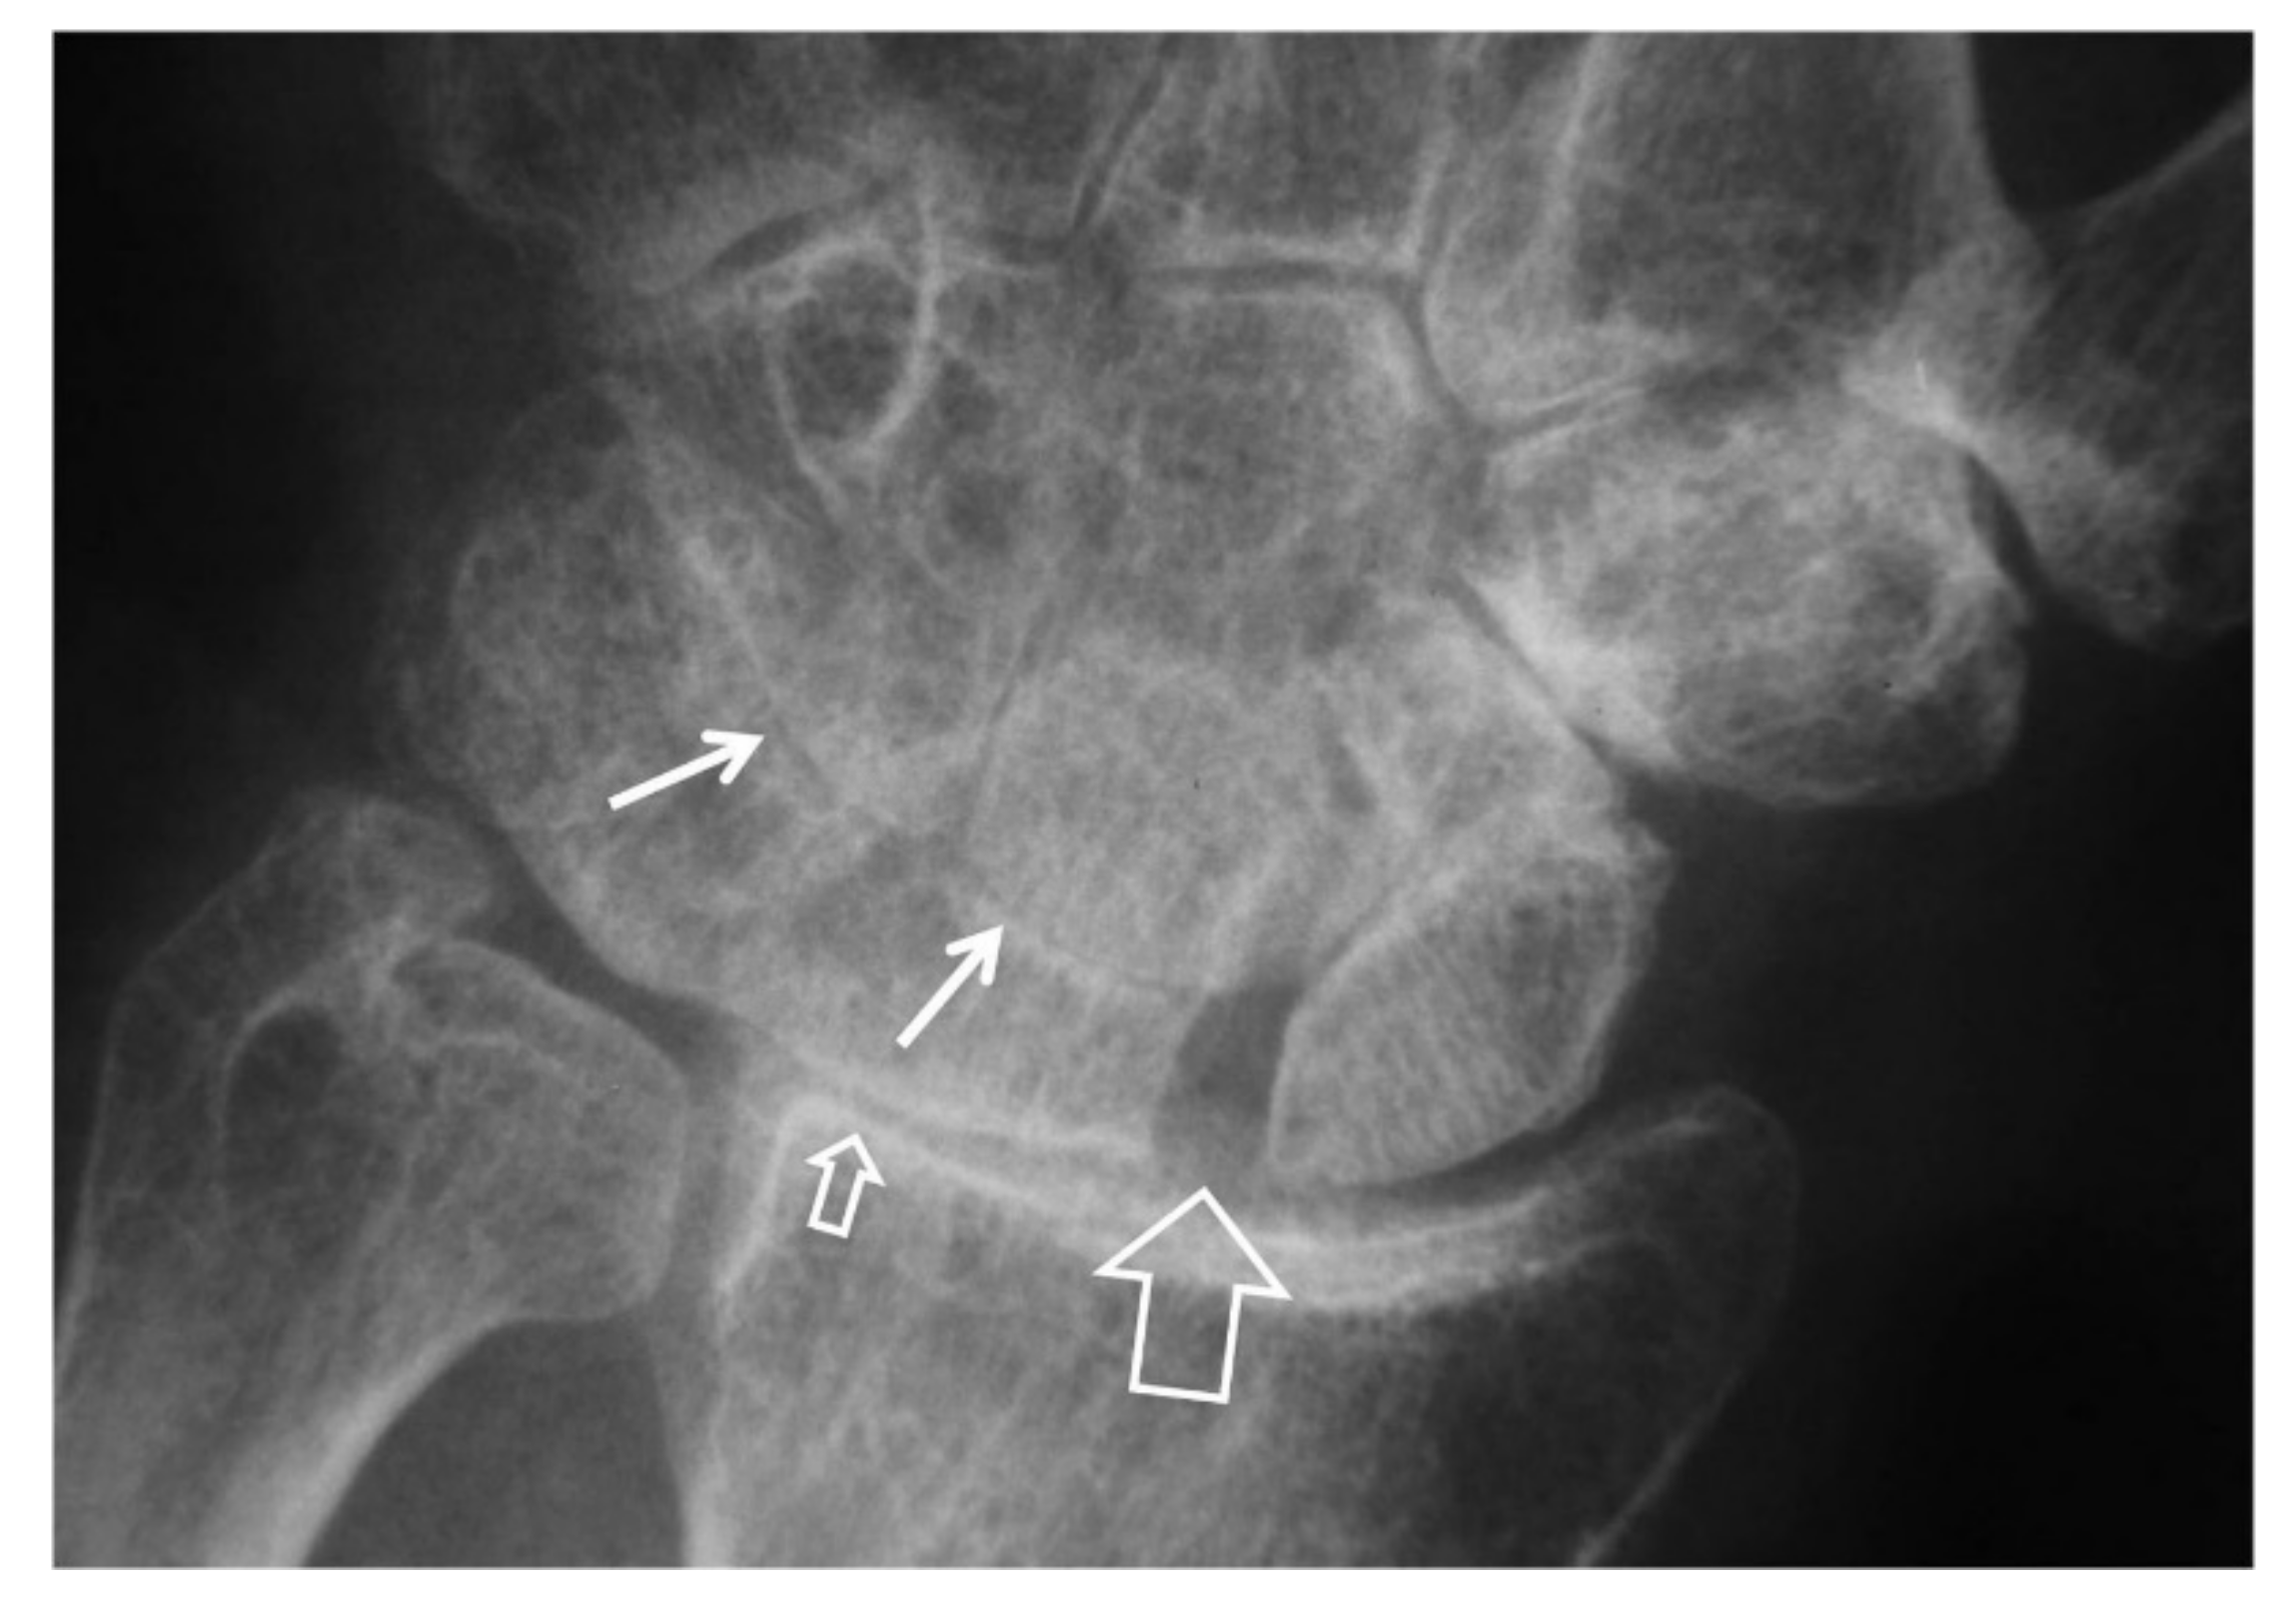

Concerning DISI, the imaging findings in lateral radiographs are a radiolunate angle of >10°, a capitolunate angle of >30° and/or a scapholunate angle of >80° [7]. Particularly for SNAC, radiographs can also detect the non-union scaphoid fracture and the induced avascular necrosis (AVN) of the proximal scaphoid fragment (Figure 5). Knowing the vascular supply to the scaphoid is valuable in understanding AVN. The primary internal vascular supply enters the scaphoid dorsally (at 70%) mainly to its distal pole. The remaining 30% enters the scaphoid palmary, also through the distal pole. Since the scaphoid’s predominant blood supply has a distal to proximal orientation, the proximal scaphoid fragment may disrupt the blood supply and end up at the AVN of the scaphoid. AVN is associated with the position of the fracture, with the proximal fragments having a 100% chance of AVN. The primary radiographic finding of AVN of the proximal scaphoid fragment is its irregular contour with sclerotic and lytic lesions. The rest of DISI and OA findings in the radioscaphoid joint may also be present in SNAC similar to the way they are presented in SLAC [8].

Figure 5.

Scaphoid pseudarthrosis and early SNAC wrist, in this 25-year-old male patient with an injury 4 years prior to current imaging. PA radiograph (A) showing the pseudarthrosis (long arrow), proximal and distal pole osteonecrosis (small arrows) and joint space narrowing at the most radial aspect of the radioscaphoid joint (open arrow). Coronal CT reconstruction (B), showing in addition osteophyte formation of the scaphoid bone (arrow).